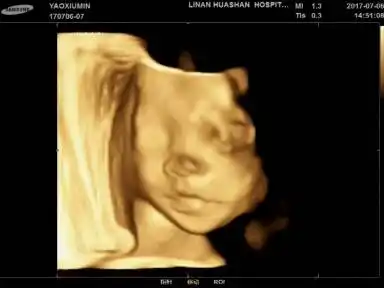

各位大姐帮忙看下宝宝四维彩超头像鼻子正常吗?